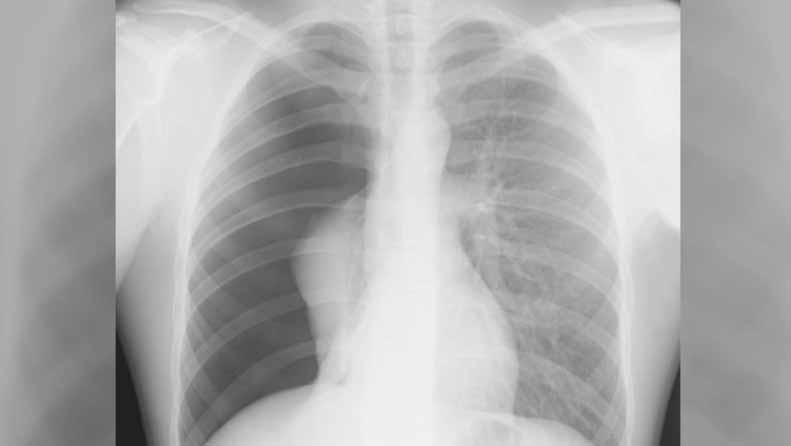

پنومونی به معنی عفونت ریه های شما است. دو نوع پنومونی وجود دارد: ویروسی و باکتریایی.

دکتر ادلمن می گوید : “معمولا تنگی نفس با پنومونی ویروسی رایج است که گاهی اوقات به آن پنومونی سرپایی نیز گفته می شود. این نوع همچنین نسبت به ذات الریه باکتریایی راحت تر است و معمولا ظرف یک تا سه هفته پاک می شود. به طور کلی ذات الریه باعث می شود که مجاری هوایی شما ورم کند و کیسه های هوایی در ریه های شما پر از خلط شود و به تنگی نفس و خستگی منجر شود.”

پنومونی باکتریایی می تواند به طور ناگهانی و یا طی چند روز بروز کند و همچنین ممکن است تب بالا را به همراه داشته باشد. پنومونی ویروسی معمولا در عرض چند روز ظاهر می شود و می تواند بسیار شبیه آنفولانزا باشد. پنومونی باکتریایی می تواند با آنتی بیوتیک درمان شود. داروهای ضد ویروسی هم ممکن است به پنومونی ویروسی کمک کنند.

همچنین واکسن هایی ضد باکتری پنومونی باکتریایی که شایع ترین علت پنومونی باکتریایی هستند، برای کودکان خردسال، بزرگسالان مسن تر و افراد مبتلا به شرایط سلامتی خاص توصیه می شود.